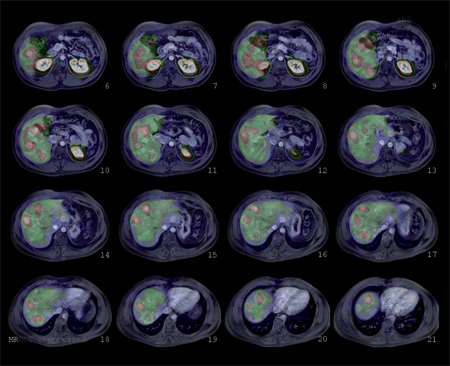

Tumores gastroenteropancreáticos

Es un tumor endocrino del páncreas muy poco frecuente, se calcula su incidencia anual en 0,5-3 casos por millón de habitantes. Casi siempre está ubicado en el páncreas (1/3 en la cabeza, 1/3 en el cuerpo y 1/3 en la cola) aunque puede tener localizaciones ectópicas: duodeno, divertículo de Meckel, vía biliar, ovario y omento. Generalmente son pequeños: 40% son menores de 1 cm y 50% entre 1 y 5 cm y generalmente solitarios. Menos del 10% son múltiples, en cuyo caso debe descartarse síndrome de NEM tipo 1. Menos del 10% son malignos y 5% se presentan con metástasis, generalmente en el hígado o adenopatías regionales27 (Figura 10). Los insulinomas benignos y malignos suelen expresar receptores de somatostatina, el más frecuente es el subtipo 4 (80-90% de los casos), de moderada (10-50%) a gran intensidad (> 50% de las células tumorales) en los estudios inmunohistoquímicos. Los subtipos 1, 2 y 3 se expresan esporádicamente (40-50% de los casos) en los insulinomas benignos y malignos,generalmente en menos del 10% de las células neoplásicas. Los insulinomas benignos no expresan sstr 5 mientras que algunos malignos sí lo hacen28. Estos hallazgos están en línea con la experiencia clínica: aproximadamente el 50% de los insulinomas son positivos en la cintigrafía con pentatreotide y el tratamiento con radiopéptidos análogos de somatostatina (Lu177-DOTATATE o Y90-DOTATOC) es paliativo y sirve para ayudar al control de la hipoglicemia de estos enfermos29 (Figura 11).

Fusión SPECT/RM. Imágenes transaxiales de RM y SPECT con In111- pentatreotide.

Paciente con insulinoma metastásico. Se demuestra intensa sobreexpresión de receptores de somatostatina en metástasis hepáticas múltiples.